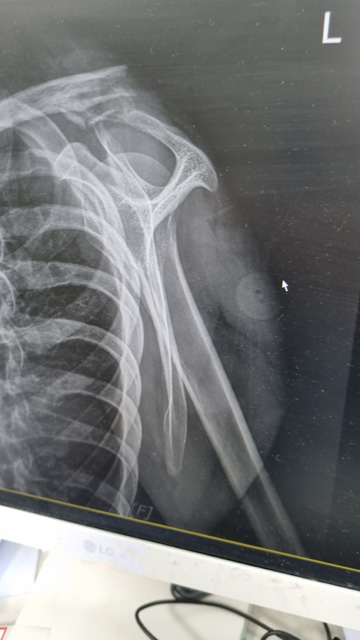

시은 쇄골 골절 2023.3.13

왼쪽 쇄골 골절입니다.

수술을 위해 바로 아빠가 근무하는 병원으로 그 날 밤 옮겨왔고 2023.3.14 화요일 수술을 받습니다.